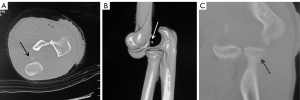

All cases were evaluated by X-ray and computed tomography (CT) examinations on the wrist and elbow joints before operation (Figures 1,2). Fractures classifications of the 13 patients are shown in Table 1. The radial head fractures were categorized based on the Mason classification, including 1 case of type I, 7 cases of type II, and 2 cases of type III. There were 2 cases that were combined with radial neck fractures.

For the management of the acute combined injuries of the ipsilateral wrist and elbow joints, comprehensive and systematic examinations prior to treatment are very important. It is not only necessary to select requisite clinical imaging detection methods to accurately determine the specific types of fractures and dislocations’ but also to reasonably evaluate the severity and scope of soft tissue injuries. When treating all elbow fractures or dislocations, the X-ray film of the elbow and wrist joints should be routinely examined. When the wrist receives a great violent external force, the cancellous bone structure at the distal end of the radius bone makes it prone to comminuted fractures and severe displacement, and may also combine with carpal fracture or dislocation. Among them, the incidence of combined scaphoid fractures is relatively high (17). There were 4 cases of scaphoid fractures in this study, accounting for 36.4% (3/11) of the distal radius fractures. Meanwhile, CT scan and 3-dimensional (3D) reconstruction are more reliable than conventional X-ray photograph and accurately reflect abnormalities in fractures or dislocations.